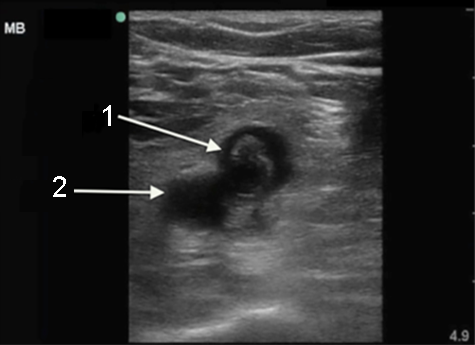

Imagen 1 de trombosis venosa profunda (TVP), trombo en la vena poplítea

1. Vena poplítea/trombosis venosa profunda (TVP) crónica

2. Arteria poplítea